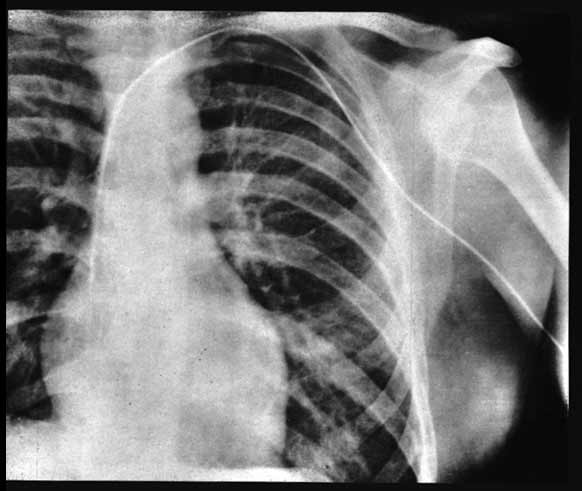

He didn’t get a permission by the clinic to do his experiment. Ignoring his department chief, Forssman persuaded the operating-room nurse in charge of the sterile supplies, Gerda Ditzen, to assist him. She agreed, but only on the promise that he would do it on her rather than on himself. However, Forssmann tricked her by strapping her to the operating table and pretending to locally anesthetize and cut her arm whilst actually doing it on himself. He anesthetized his own lower arm in the cubital region and inserted a uretic catheter into his antecubital vein, threading it partly along before releasing Ditzen (who at this point realized the catheter was not in her arm) and telling her to call the X-ray department. They walked some distance to the X-ray department on the floor below where, under the guidance of a fluoroscope, he advanced the catheter the full 60 cm into his right ventricular cavity. This was then recorded on X-Ray film showing the catheter lying in his right atrium.